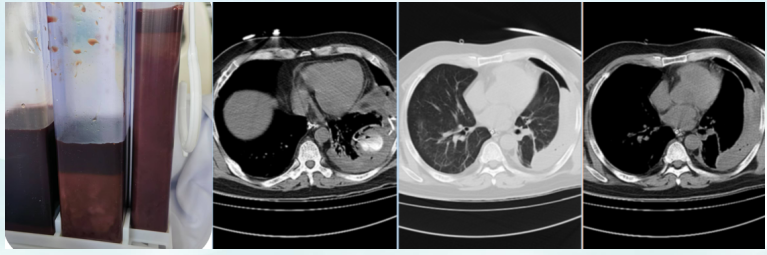

5月5日复查胸部CT:肺渗出病灶较前吸收,右上肺厚壁空洞,左侧胸腔血气胸伴左肺膨胀不全(图7)。支气管动脉CTA示:支气管动脉未见明显异常,未见肺占位;左肺下叶簇状瘤样改变,内见造影剂充盈,边缘光滑清晰,考虑血管改变,三维重建与左肺下叶动脉相连(图8),符合肺动脉瘤诊断。

图片

7  患者胸部CT(2025-05-05)

8  患者支气管动脉CTA(2025-05-05)